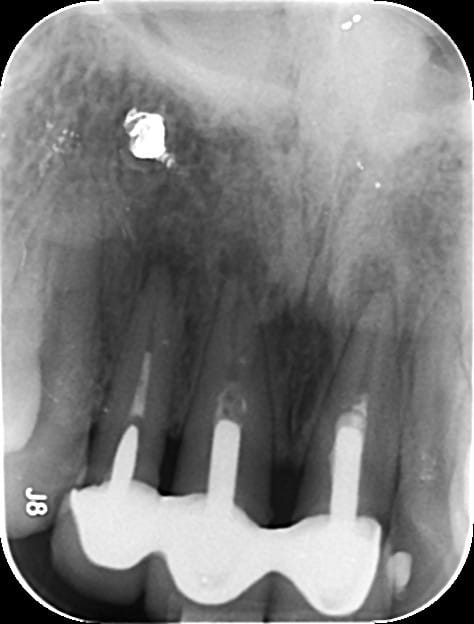

Les densités à la radio et le paralèlisme des tenons laissent penser à un bloc de richmonds solidarisées.

On peut espérer en la faiblesse du ciment.

Il s'agissait de reconstitution foulé Compo + tenon metalliquecollés au Fuji . Tenon que je n'avais jamais vu auparavant ( rainure sur toute la longueure) .

Dépose sans trop de casse et endo correcte dans la foulée .